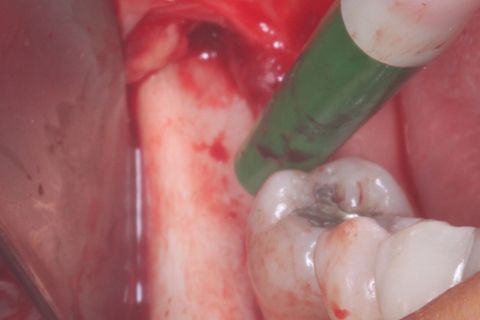

Área doadora: Ramo mandibular ascendente lado direito

Área doadora: Ramo mandibular ascendente lado direito, após a remoção do bloco ósseo.

Bloco ósseo removido.